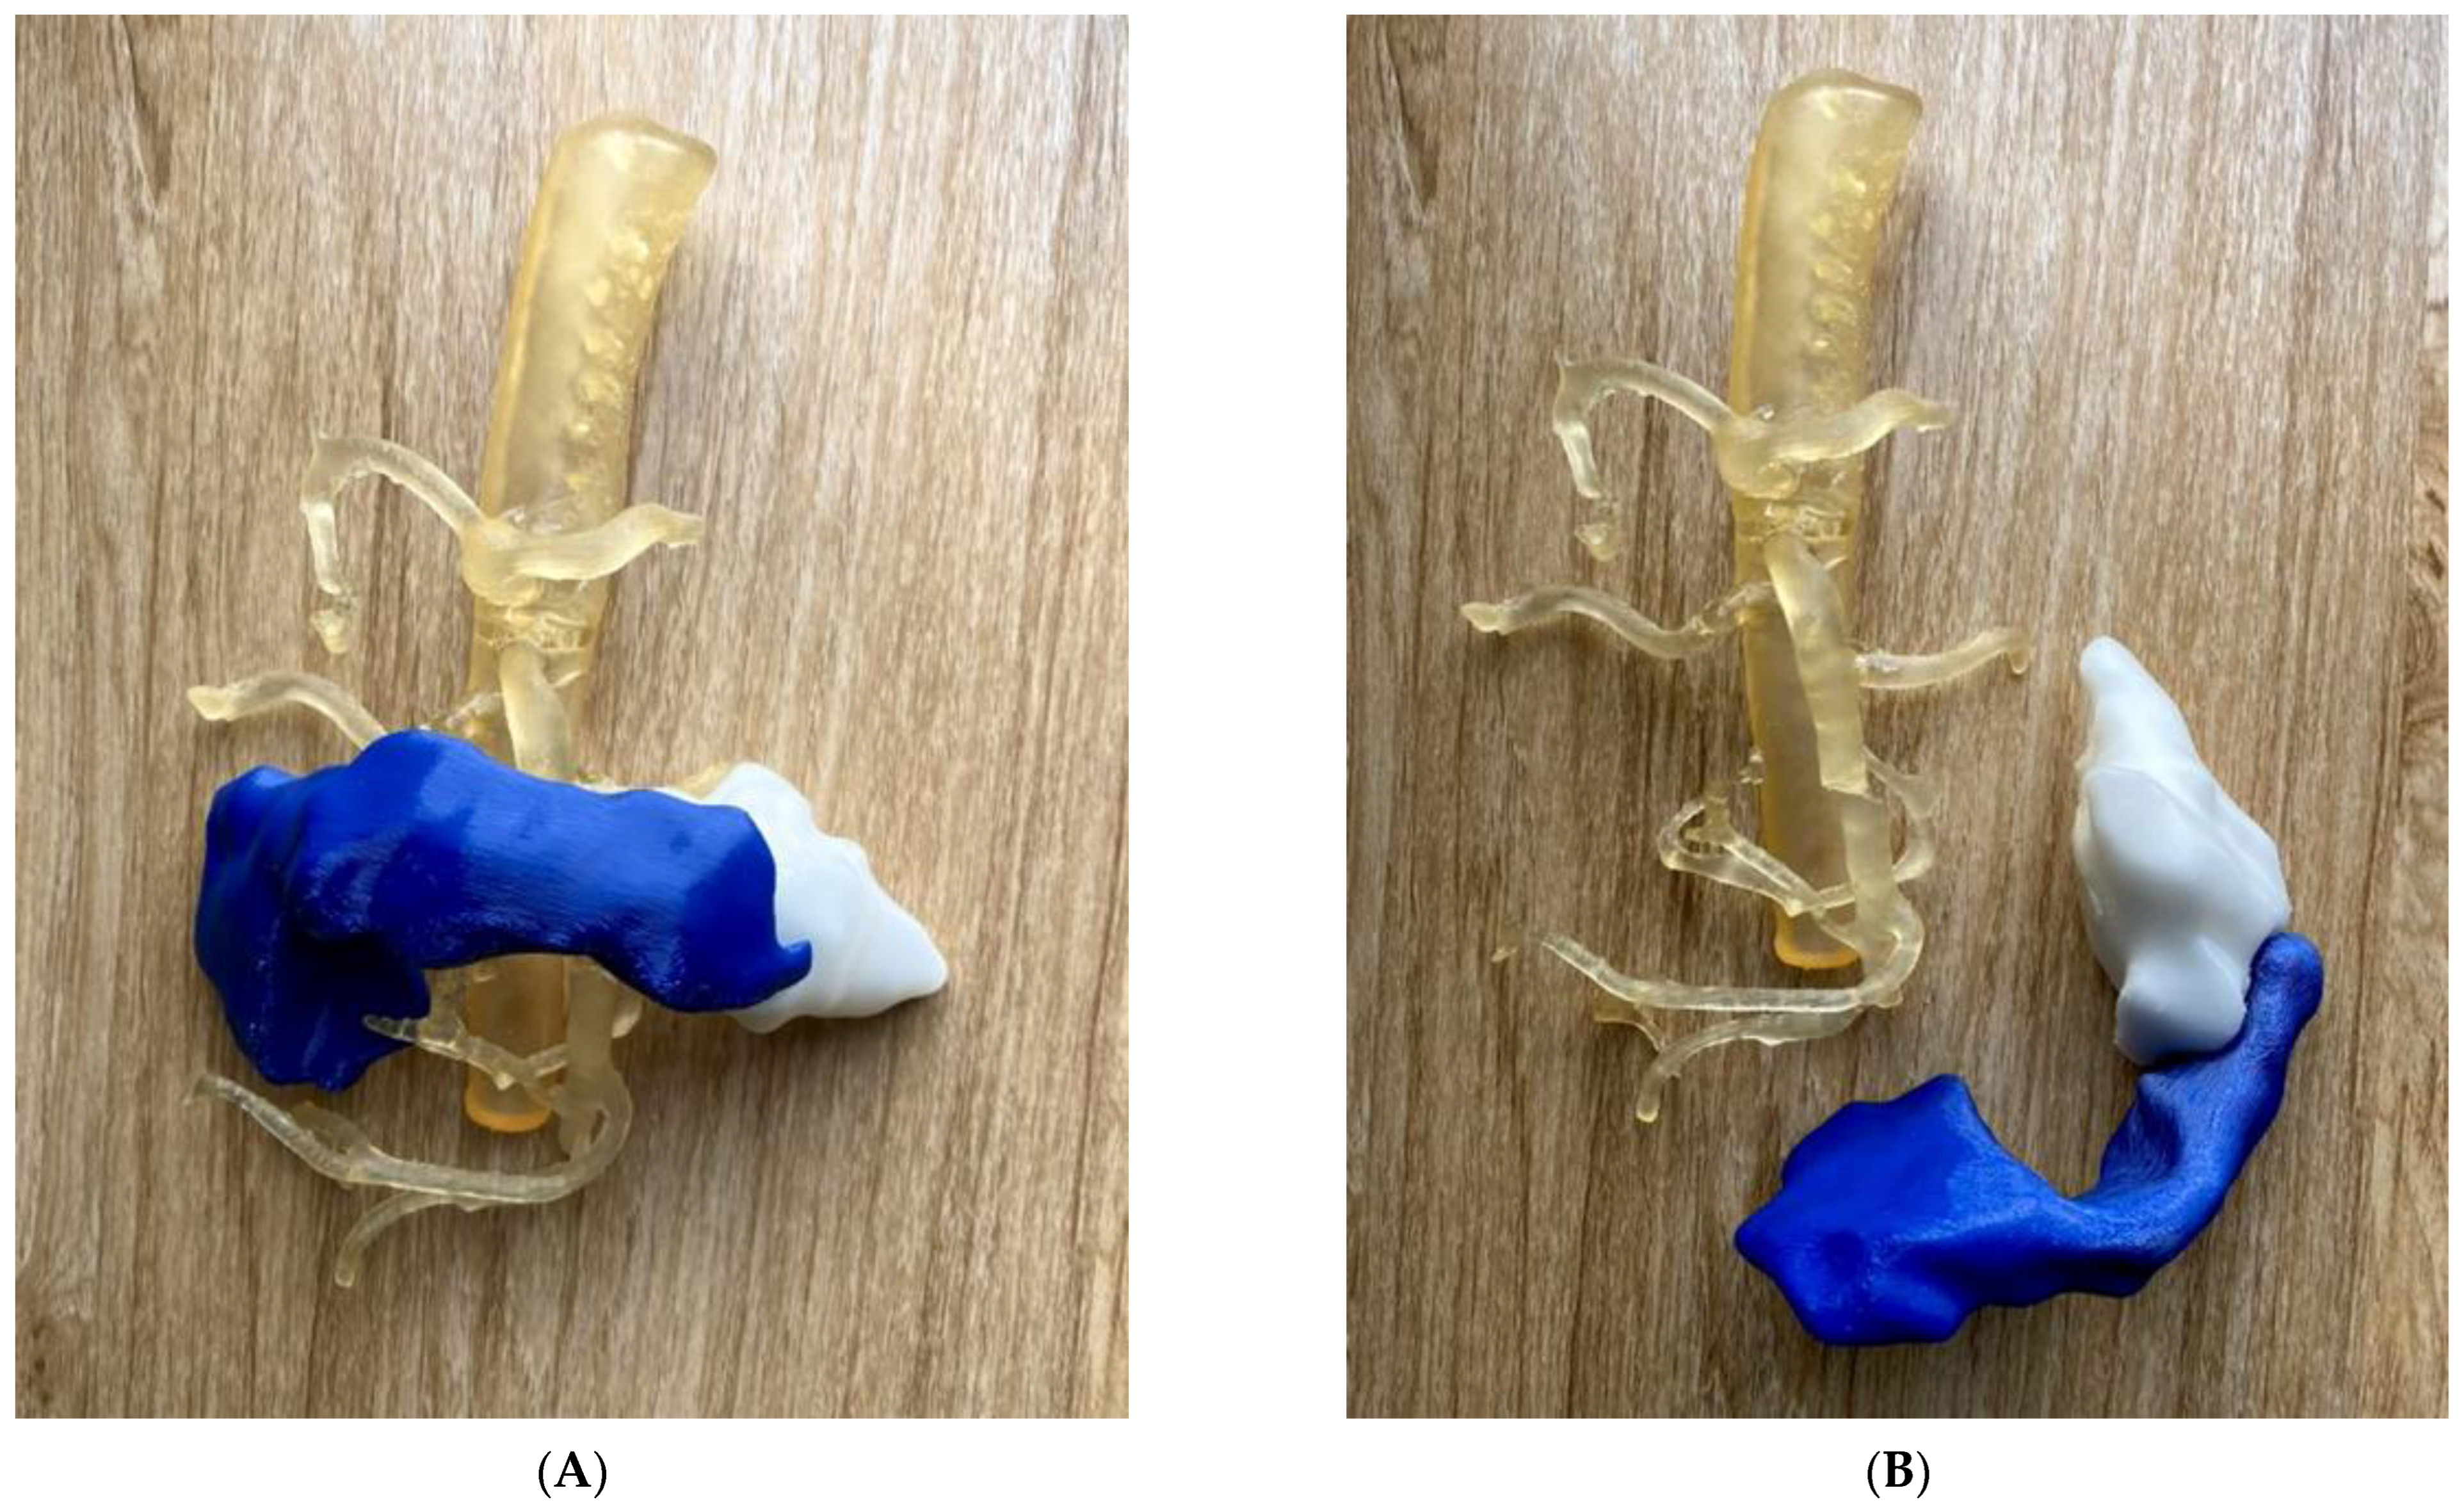

5.5. 3D-Printed Biliary Cyst Model

| Biliary cyst | 1 | CT | Accuracy and preoperative planning | Ultimaker 2+ Extended Material: TPU 95A Cost: USD 35 | Model was printed at a resolution of 12.5 μm for the x, y and z-axis plane Time: ~70 h |